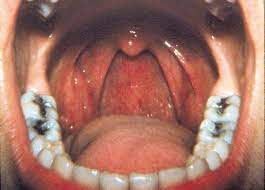

How Do You Know If You Have Throat Cancer From Hpv : World First Saliva Test Detects Hidden Throat Cancer Clinical Knowledge Network / Cancer usually develops several years after hpv exposure, and may be concurrently linked to alcohol and tobacco usage.. Cancers in the region of the head and neck that we call the oropharynx, which includes the tonsils and the base of the tongue so the part of the tongue that's behind what you can actually see in your mouth. Hpv causes head and neck cancers too. It can also cause cancer in the back of the throat, including the base of the tongue and tonsils (called oropharyngeal cancer). The virus doesn't cause symptoms, and most of the time, your immune system clears the infection from your body within 2 years. Personally, i'm excited to know that there is a vaccine that can prevent my type of throat cancer.

Oropharyngeal Cancer What Is It Symptoms Stages Prognosis from www.clevelandclinic.org Hello everyone, my name is sam, 24. Experts are using the word epidemic to describe it. Your doctor might notice signs of throat cancer or oral hpv during a routine exam. These cells can develop from oral hpv. Hpv is not transmitted by casual contact. Prendes says, because they're difficult to recognize and categorize. Partners of someone with hpv related mouth/throat cancer do not have an increased rate of oral hpv infection. If any of the symptoms lasts beyond two weeks, see your doctor or an ear, nose and throat specialist.

Most people with hpv don't have any symptoms and their immune system will get rid of the hpv infection without any treatment. Symptoms of oral and throat cancers (from any cause) include a swelling or lump in the mouth, a painless lump on the outside of the neck, an enlarged tonsil, and a sensation of having a foreign. It can also cause cancer in the back of the throat, including the base of the tongue and tonsils (called oropharyngeal cancer). Having a weakened immune system. If you have oropharyngeal cancer, cancer cells form in the middle of the throat, including the tongue, tonsils, and pharynx walls. Hello everyone, my name is sam, 24. I admit i believe everything i see from dr google, bad habits i know. But in some cases, after many years,. Hpv can cause cervical and other cancers including cancer of the vulva, vagina, penis, or anus. Partners of someone with hpv related mouth/throat cancer do not have an increased rate of oral hpv infection. Hpv infection very rarely leads to a cancer. The sample is sent to a laboratory for testing. There's no standard screening test to find these cancers early.

Quitting smoking can help your body to fight hpv. But, it can sometimes be difficult to know whether you have it. Hpv causes head and neck cancers too. Symptoms of oral and throat cancers (from any cause) include a swelling or lump in the mouth, a painless lump on the outside of the neck, an enlarged tonsil, and a sensation of having a foreign. Some throat cancers are thought to be caused by the sexually transmitted infection human papillomavirus (hpv). In fact, the number of people diagnosed with. Having a weakened immune system. Therefore, if you notice any changes in your health, you should consult with an experienced physician right away. Hpv can infect the mouth and throat and cause cancers of the oropharynx (back of the throat, including the base of the tongue and tonsils). The tissue sample may also be tested for hpv, since the presence of this virus impacts the treatment options for certain types of throat cancer. Most people clear hpv within one to two years, but hpv infection persists in some people. You can reduce your risk of hpv by limiting your number of sexual partners and using a condom every time you have sex. (they are represented by the roman numerals i, ii, iii, and iv.) these are the basic stages of throat cancer:

If you have oropharyngeal cancer, cancer cells form in the middle of the throat, including the tongue, tonsils, and pharynx walls. But, it can sometimes be difficult to know whether you have it. It can also cause cancer in the back of the throat, including the base of the tongue and tonsils (called oropharyngeal cancer). I admit i believe everything i see from dr google, bad habits i know. That didn't exist when i was young, but i wish it had. Infections with hpv are common. Hpv causes head and neck cancers too. Cancers in the region of the head and neck that we call the oropharynx, which includes the tonsils and the base of the tongue so the part of the tongue that's behind what you can actually see in your mouth. Partners of someone with hpv related mouth/throat cancer do not have an increased rate of oral hpv infection. But in some cases, after many years,. If you have either of these hpv types, make sure you receive diagnostic testing with a colposcopy. Cancer usually develops several years after hpv exposure, and may be concurrently linked to alcohol and tobacco usage. Quitting smoking can help your body to fight hpv.